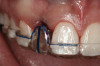

Figure 6  Characterization of the interproximal bone and tooth contacts: A periapical radiograph assists in measuring the distance from bone crest to the adjacent tooth contact points for missing tooth No. 8. The mesial bone crest to the adjacent tooth contact distance is < 5 mm, while the distal bone crest to adjacent tooth contact distance is > 6 mm (Fig 4). One-year following implant placement, conservation of these dimensions is revealed (Fig 5). The clinical photograph (Fig 6) of the lateral incisor adjacent to tooth No. 8 implant crown demonstrates that the absence of distal interproximal (papilla) fill related to the observed bone crest to contact distance exceeds 6 mm.

Figure 6

Figure 4  Characterization of the interproximal bone and tooth contacts: A periapical radiograph assists in measuring the distance from bone crest to the adjacent tooth contact points for missing tooth No. 8. The mesial bone crest to the adjacent tooth contact distance is < 5 mm, while the distal bone crest to adjacent tooth contact distance is > 6 mm (Fig 4). One-year following implant placement, conservation of these dimensions is revealed (Fig 5). The clinical photograph (Fig 6) of the lateral incisor adjacent to tooth No. 8 implant crown demonstrates that the absence of distal interproximal (papilla) fill related to the observed bone crest to contact distance exceeds 6 mm.

Additional attention must be paid to the osseous architecture related to the adjacent teeth, as this controls interproximal tissue form.7 The crest of healthy bone is 4.5 mm to 5 mm from the contact point between anterior teeth8; a similar 5-mm distance from the contact point to the bone crest has been measured between an implant and natural tooth. An important and additional rule to guide esthetic implant outcomes is that the adjacent tooth should possess interproximal bone levels no further than 6 mm from the natural tooth contact point (Figure 4 through Figure 6). While the ideal distance is justifiably indicated to be 5 mm, this 6-mm rule establishes a point at which marked interproximal tissue deficiencies and asymmetry will not be overcome.